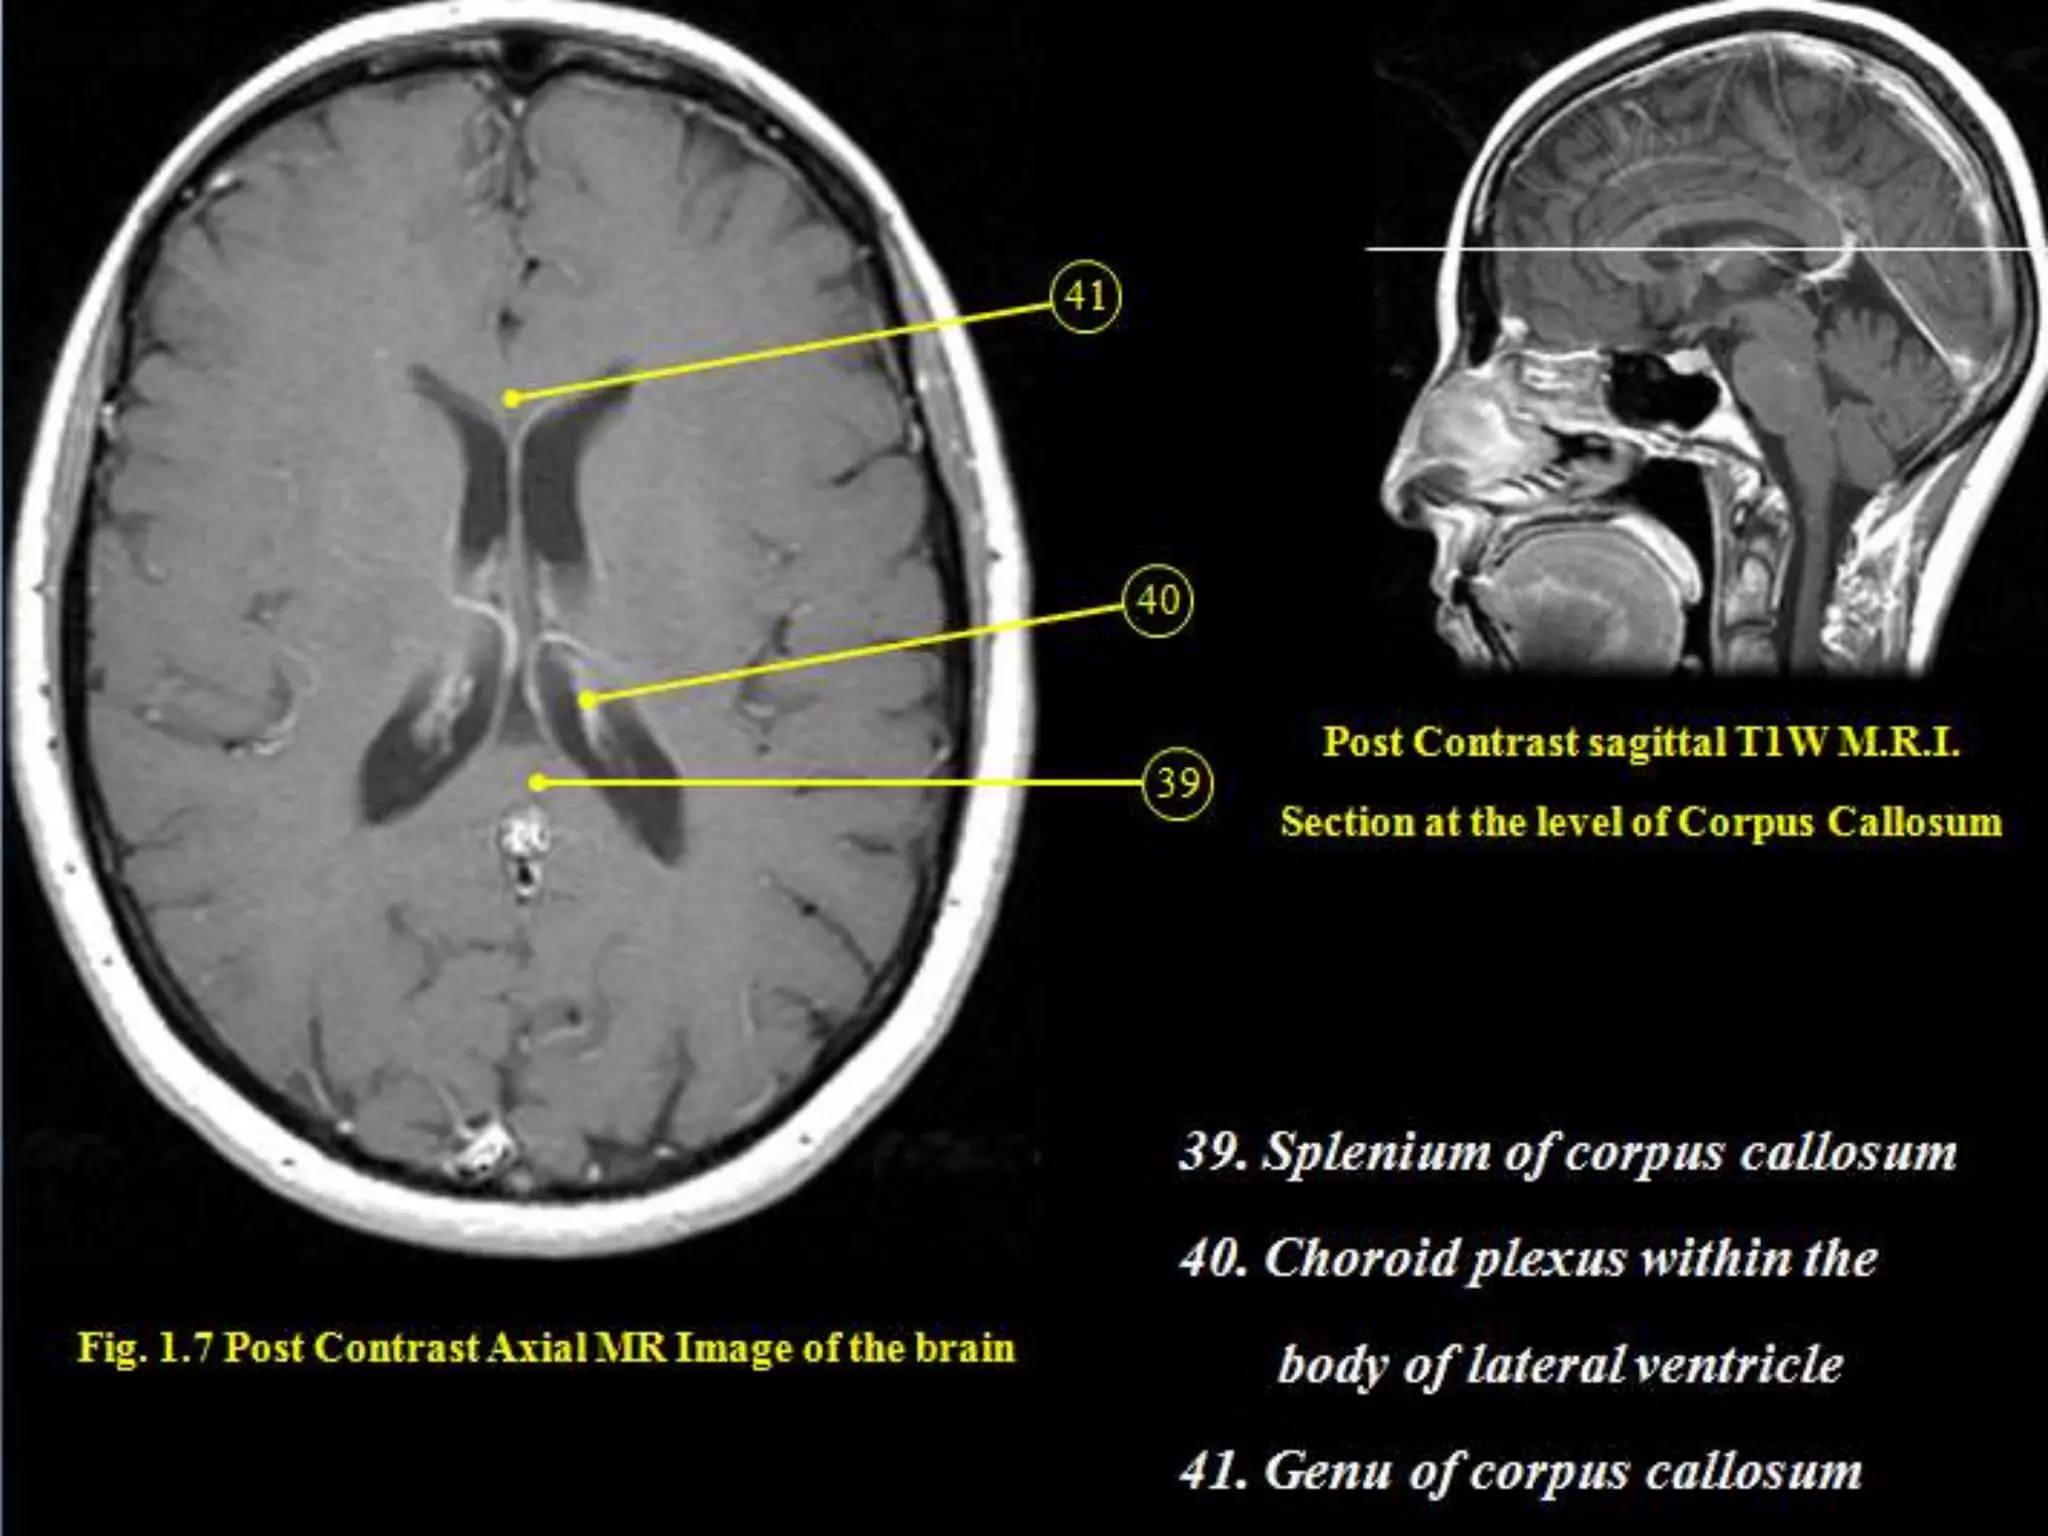

The Corpus Callosum.

Sectional Anatomy: NormalAxial CT and MRI Anatomy. On CT and MR scans, the brain has been briefly viewed in infratentorial and supratentorial sections, as described below. CT scans are performed with a 15- to 20-degree angulation to the canthomeatal line at 8-mm increments. MRI scans are generally obtained parallel to the AC-PC line in the axial plane with 6-mm slice thickness. Using the sagittal view, the coronal sections are acquired parallel to the brain stem, and the sagittal sections are obtained perpendicular to the axial section. On MRI studies, cranial nerves IX and X can be demonstrated at this level because they emerge from the postolivary sulcus. The posterior aspect of the cerebellar hemispheres is outlined by the inferior portion of the cisterna magna.